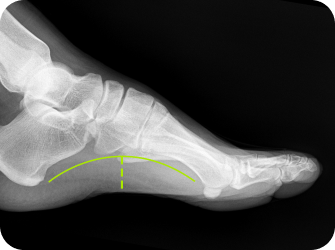

유연성 평발이 있는 경우에는 평발의 교정이 필수입니다.

중족골 내전

발이 안쪽으로 휘어 있는 경우

족궁 높이 측정

발 뒤꿈치 각도 검사

평발, 요족, 까치발,

발의 변형 등 족부 문제를

맞춤형 깔창으로 교정

유연성 평발이 있거나 구조적 문제가 동반된 경우 시간이 지나도 좋아지지 않습니다.